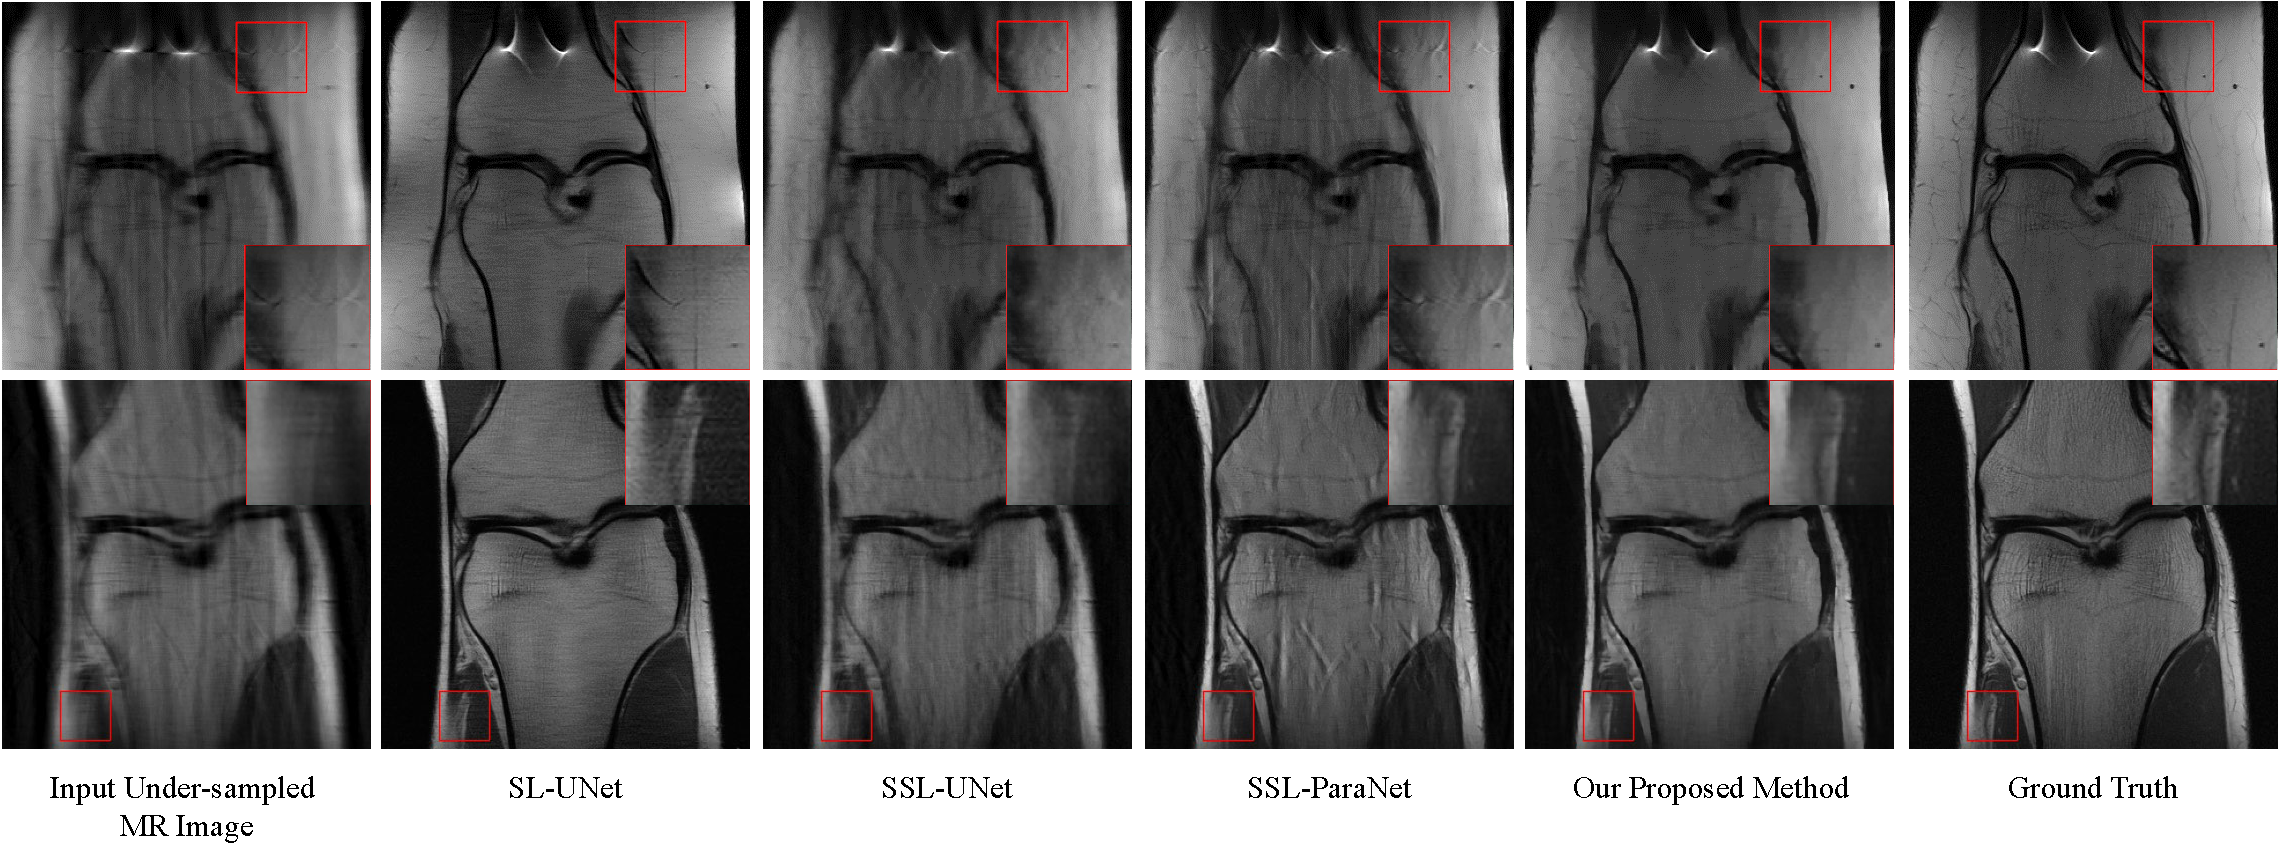

Visual Comparisons